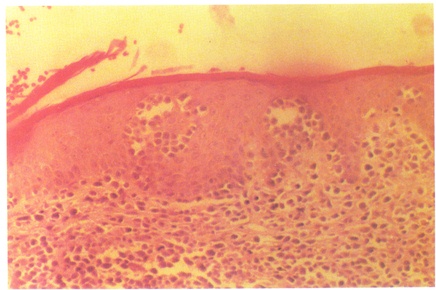

蕈样肉芽肿组织病理象